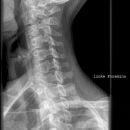

HWS seitlich

Es wurden keine Bilder gefunden.

Kassette/Abstand

Format 24/30 hoch oder 18/24 hoch/ FFA 1,15m

Lagerung

Patient sitzt seitlich am Wandstativ, Schulter nach unten ziehen, Medianebene parallel zum Stativ, Kassette erstreckt sich von Tragus bis Jugulum.

Zentralstrahl

Senkrecht auf hinteres Drittel der HWS (2-3 QF) und Kassettenmitte, bzw. auf Muskelstrang (M. sternocleidomastoideus) des Halses.

Indikation

Bei Schleudertrauma (traumatische Läsion), degenerative Veränderungen.

Qualitätskriterien

Alle 7 HWK lateral dargestellt, orthogonale Darstellung der Grund- und Deckplatten, Processus spinosus des 7. HWK vollständig dargestellt, Mandibula überdeckt HWS nicht.